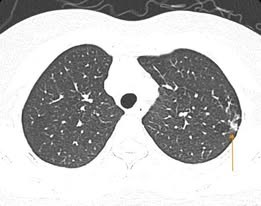

Tại đây, người bệnh được chẩn đoán mắc cúm B bội nhiễm và được chỉ định điều trị bằng kháng sinh, kháng virus cúm, kết hợp các biện pháp hỗ trợ như giảm ho, hạ sốt và bù nước điện giải.

Khi tình trạng diễn biến nặng hơn người bệnh mới đến Bệnh viện E thăm khám và được chẩn đoán mắc cúm A bội nhiễm. Tại Bệnh viện, người bệnh được điều trị bằng kháng sinh, kháng virus cúm kết hợp các biện pháp hỗ trợ như giảm ho, hạ sốt và bù nước điện giải.

Mặc dù nhiều trường hợp cúm có thể tự hồi phục, nhưng nếu không được điều trị kịp thời, bệnh có thể diễn biến nặng, gây biến chứng nguy hiểm như viêm phổi, suy hô hấp, bội nhiễm vi khuẩn, thậm chí đe dọa tính mạng ở những trường hợp nặng.